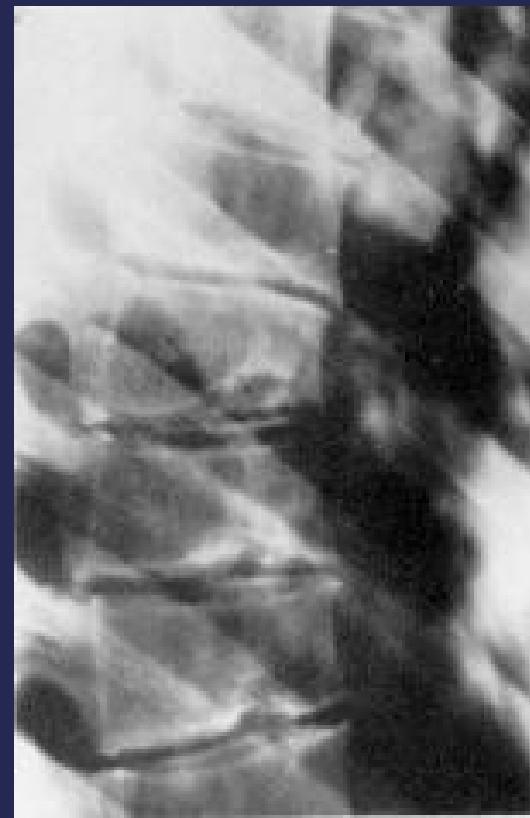

Scheuermann’s Disease

Pathology:

- Irregular ossification of vertebral body epiphysis

- Central herniation of disc material into the body (Schmorl’s Node)

- Wedging of vertebrae

Radiographic Findings:

- Schmorl’s nodes -Central herniation of disc material into the body

Pathology

X-ray Findings

- Schmorl’s nodes (central disc herniation)

- Vertebral wedging